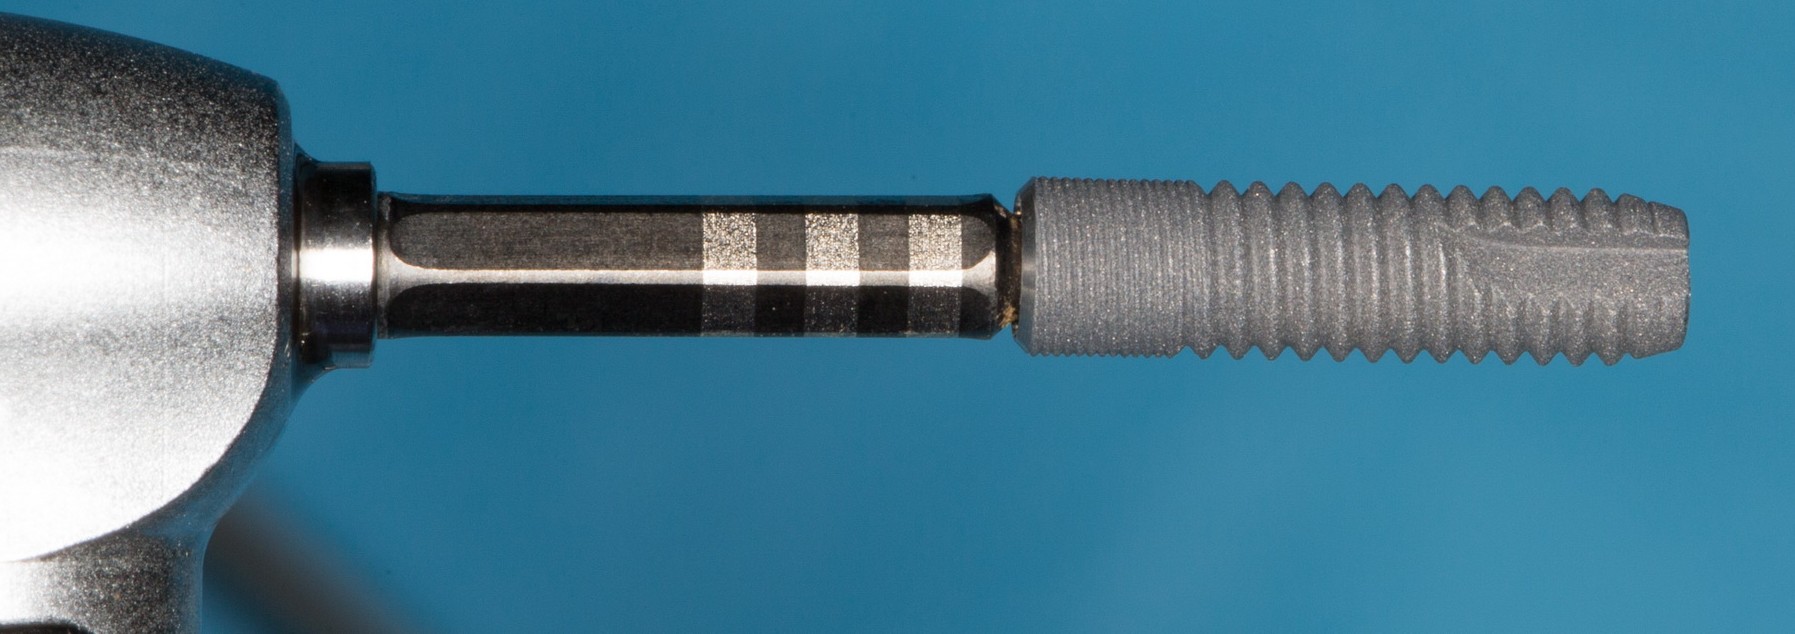

В связи с этим, мы выбираем имплант Dentsply Astratech диаметром 3.5 и длиной 13 мм. Это — минимальный диаметр импланта, на котором возможно эстетическое протезирование. Под данный размер платформы есть полный набор супраструктур — и это облегчает работу ортопеду.

Устанавливаем имплантат в лунку зуба:

Обратите внимание на глубину погружения импланта и расстояние от его стенки до корня зуба. Не нужно пытаться добиться высокой первичной стабильности путем чрезмерного погружения импланта. Это создаст сложности при протезировании. Лучше выставить его в правильное положение с оглядкой на соседние зубы (шейка импланта на уровне шеек естественных зубов), забыть про первичную стабильность (не так важна, как кажется) и недостаток окружающих тканей. Последние можно восстановить остеопластическими методами.